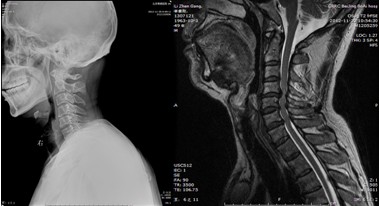

患者,男性,49岁,主因“行走不稳2个月伴右前臂麻木1个月”入院

2月前开始出现双下肢行走不稳,有踩棉花感,行走距离受限。1月前出现右侧前臂及手指麻木感。3周前诊断为“颈椎病”,保守治疗无改善,行走不稳症状加重

影像检查结果:

手术效果:术后当天下肢麻木无力症状即消失,术后1天,上肢麻木无力症状也好转。术后7天离床活动,自觉踩棉花感觉消失,下肢变得有力,可以正常速度上下楼,双手抓握力量明显增强,灵活性好。查体上肢肌力如屈指肌力、小指外展肌力恢复到5级,下肢小腿三头肌肌力恢复到5级。